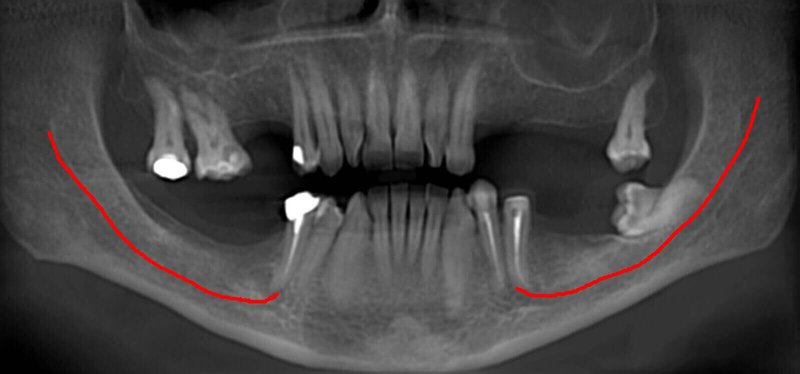

GIANO HR – универсальное обновляемое устройство от NewTom для всех задач, связанных с радиографией. Благодаря полному диапазону опций 2D и 3D исследования для стоматологии оно предлагает множество особых трехмерных обследований для челюстно-лицевой хирургии, оториноларингологии и осмотра шейного отдела позвоночника. Визуализация только наивысшего качества с технологиями и опытом NewTom

NNT – программное обеспечение NewTom, предоставляющее несколько специальных режимов применения для имплантологии, эндодонтии, пародонтологии, челюстно-лицевой хирургии и радиографии. Это мощное технологически новейшее устройство, разработанное, чтобы снимать и обрабатывать изображения в несколько простых шагов для получения информации, необходимой для конкретного подробного диагноза пациенту. Продвинутое устройство, дающее врачу специальные инструменты для измерения анатомической области (расстояния и углы), нахождения нижнего альвеолярного нерва и замера объема верхних дыхательных путей.

NewTom GiANO HR новейшая модель была официально представлена на международном конгрессе радиологов ECR 2018 в марте в Вене. Благодаря обновленным системам механики и запатентованным механизмам работы аппарат отличается от своих сверстников Высочайшим качеством получаемых изображений, как 2D, так и 3D. Лучшее качество снимков и мы отвечаем за это! Этот аппарат заменит три аппарата! Панорамный аппарат, цефалометрическая приставка и конусно-лучевая компьютерная томография интегрированы в единую платформу. В комплекте детектор для выполнения 3D исследований с захватом области 13х16 см, Сьемный 2D CMOS детектор для выполнения панорамных исследований, и ТРГ.